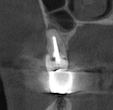

Santi Опубликовано 31 октября, 2023 Поделиться Опубликовано 31 октября, 2023 (изменено) Короткая нарезка с операции резекции 14-15. Апикально материал на основе минерал триоксид агрегата. Критике и комментам всегда рад. Изменено 31 октября, 2023 пользователем Santi 5 2 Ссылка на комментарий